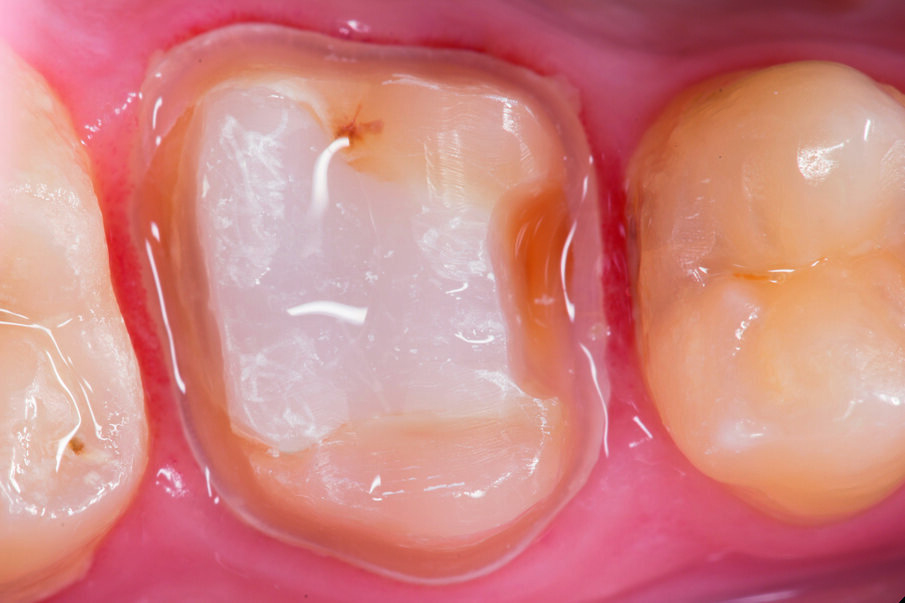

This case below shows a posterior tooth with an endodontic treatment followed by an indirect crown restoration. SDR® Plus is used as a core build up material before the crown was seated.

This case involves the use of SDR® Plus composite as a core build-up material. The outstanding flowability of SDR® Plus composite allows complete filling of the pulp cavity, even in the smallest recesses; the composite was placed in two stages to ensure thorough polymerisation. The periphery of the tooth was then prepared, preserving a layer of enamel at the preparation margin to ensure effective bonding of an all-ceramic crown. This was bonded with the Calibra® system. This protocol thus avoids iatrogenic mechanical strains on the tooth roots during core build-up. This treatment, involving a tooth/restoration monoblock with SDR® Plus composite and crown using only adhesive techniques, provides for outstanding biomechanical and aesthetic results.

Fig. 4: First layer of SDR® Plus was placed at the cavity bottom. SDR® Plus self-levels within a few seconds and can be applied to 4mm.

Fig. 5: SDR® Plus first increment was light-cured for 20 sec, before a second layer of SDR® Plus was placed and light-cured.